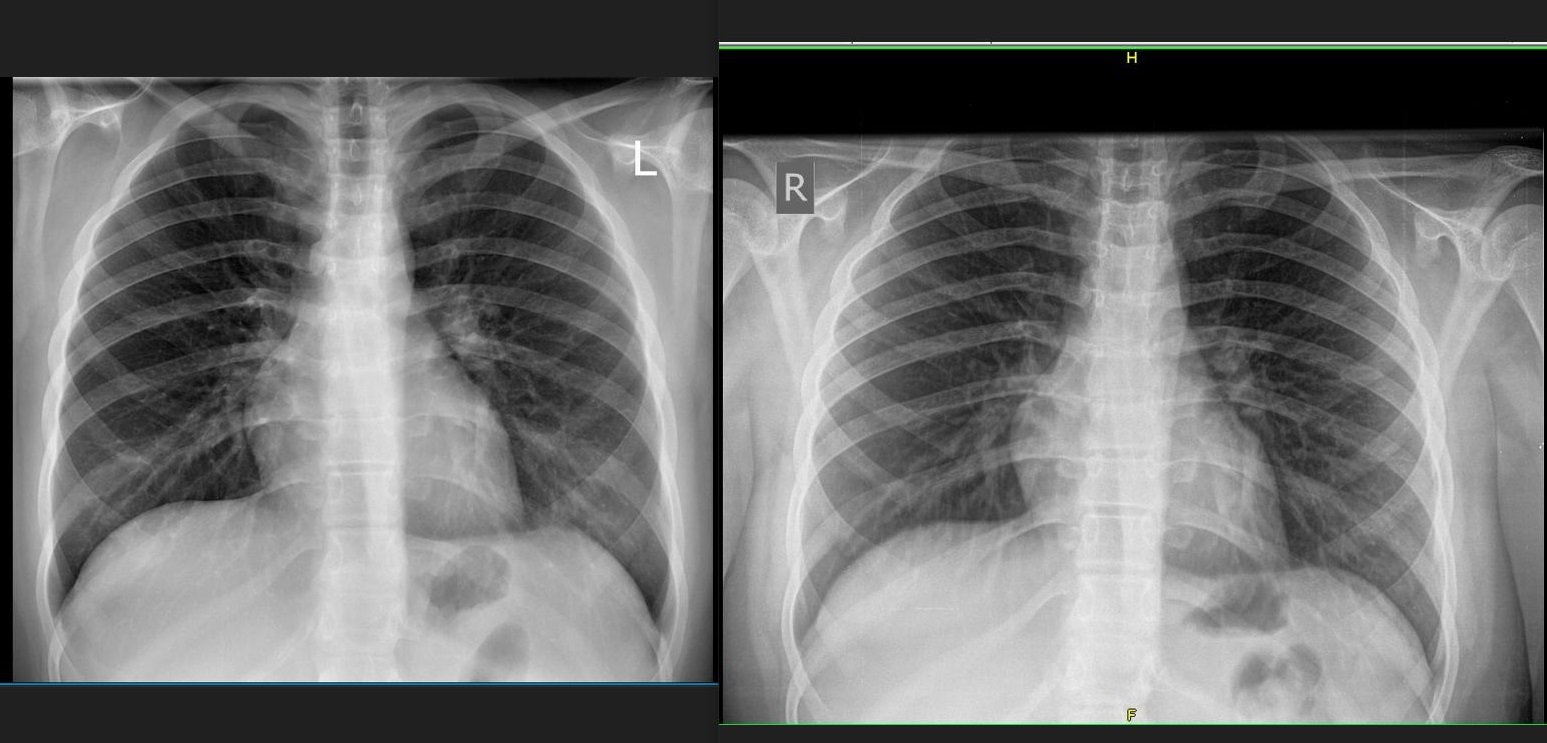

Качвам за сравнение, вляво е новата с пневмония, вдясно след излекуван бронхит преди 5 месеца:

Мисля утре да се консултирам с друг рентгенолог за тълкуване особено ако няма температура